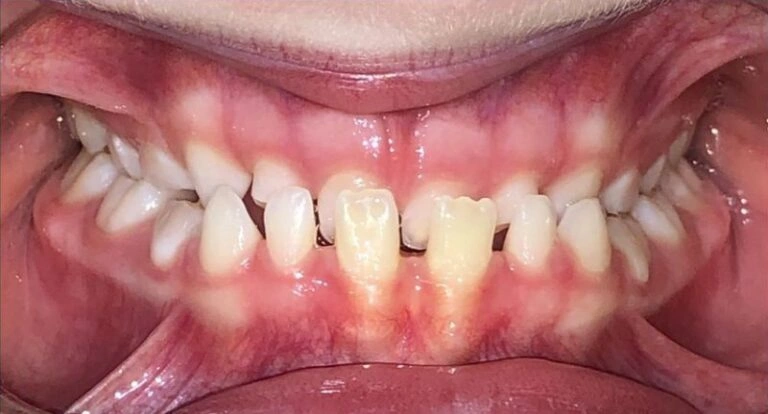

Let me tell you an incredible story: Meet Alexander, a patient of mine who was facing serious tooth problems. None of his adult teeth were coming in! His mother, Cassandra, was understandably frustrated. A dentist had told her that Alexander would need jaw surgery if an orthodontist didn’t step in. But when she visited an orthodontist, they told her that without more adult teeth, they couldn’t treat him.

Cassandra, a surgical tech, knew surgery was not her first choice. So, she came to us for help. Turns out, Alexander’s jaw was so narrow that it was preventing his adult teeth from coming in properly. His upper jaw didn’t fit with his lower jaw, and there was no space for his teeth to grow in. This is a common issue we see in kids, and it’s directly related to crowded teeth.

If we didn’t widen his jaw, his adult teeth wouldn’t have room to come in. And, as you can imagine, we wanted to avoid a situation where we’d have to extract permanent teeth down the road.

With Invisalign First, the results have been amazing. Just take a look at Alexander’s transformation! His adult teeth practically flew into place once his jaw had the space it needed.